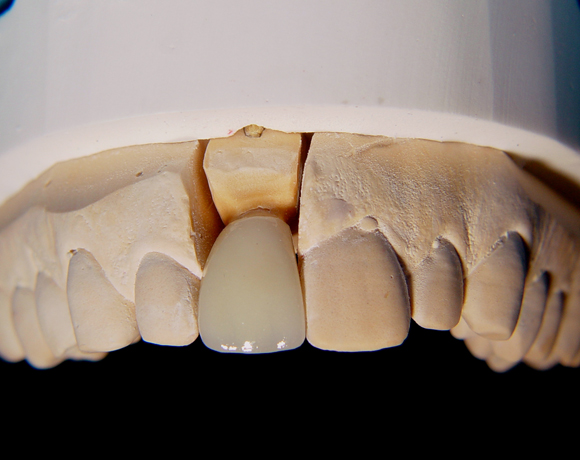

Bei diesem Patienten wurden die Nachbarzähne und das Implantat vollkeramisch versorgt.